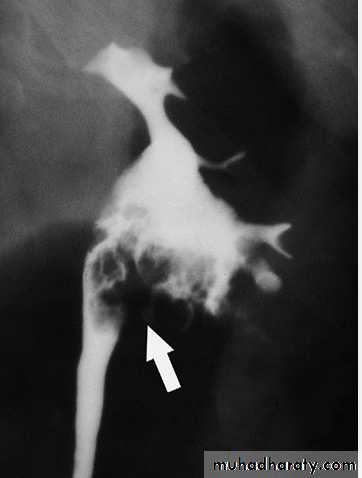

Multiple Calculi in the Renal Pelvis. A retrograde pyelogram demonstrates multiple filling defects

Radiograph from a retrograde pyelogram of the left kidney reveals a multilobulated filling defect (arrow) in the left renal pelvis. Biopsy confirmed transitional cell carcinoma.